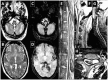

Findings: We report on the case of a 48-year-old man with history of left brachial plexus injury at the age of 2 years. Since the age of 38 years, he had presented with a progressive paraplegia, bladder and erectile dysfunction, neuropathic pain and sensory level. The diagnosis was made by spinal cord and brain magnetic resonance follow-up imaging revealing hypointensity T2-weighted gradient echo linear dark rim around the entire neuraxis and cervical dural pseudomeningoceles. These MRI findings were suggestive of extensive hemosiderin deposition consolidating the diagnosis of SS of CNS.

Conclusion/clinical relevance: Our case report illustrates diagnosis difficulties in unusual or paucisymptomatic presentations of SS. A history of brachial plexus trauma with nerve root avulsion should prompt gradient-echo T2-weighted imaging to bring out such a complication. Superficial siderosis of the CNS should be included in the panel of differential diagnosis of the parethospastic syndromes and compressive myelopathy.